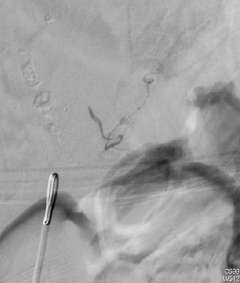

Depending on the lesion, the best treatment plan changes. For intramedullary AVMs, partial or palliative treatment is sometimes an option since complete obliteration may carry a much higher chance of causing neurological deficits than conservative management or partial treatment (Figure 3).

Figure 3: A palliative / partial Catheter Treatment for a Spinal AVM.

Multiple arteries feeding the spinal AVM. There are aneurysms in the feeding arteries.

Two feeding arteries harboring the aneurysms were obliterated using catheter embolization techniques.

The aneurysms were completely obliterated, and the risk of bleeding was reduced. However the AVM receives blood flow from the other feeding arteries.